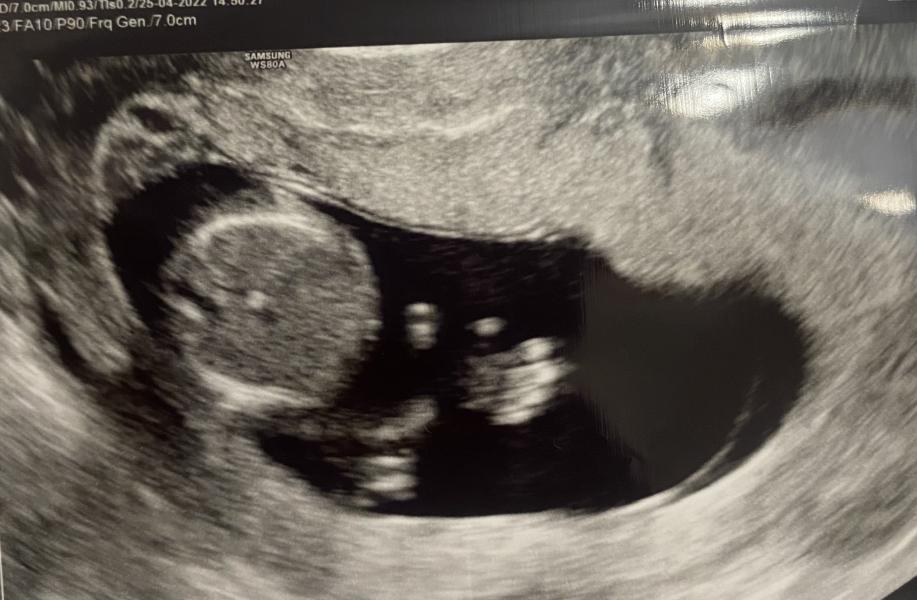

Были вчера на первом скрининге)

Какое это счастье все опять испытать по новой😊

Такая неожиданная вторая беременность, что иногда думается, что это просто сон какой то.

Пусть все пройдёт хорошо и не важно, кто в домике живет))